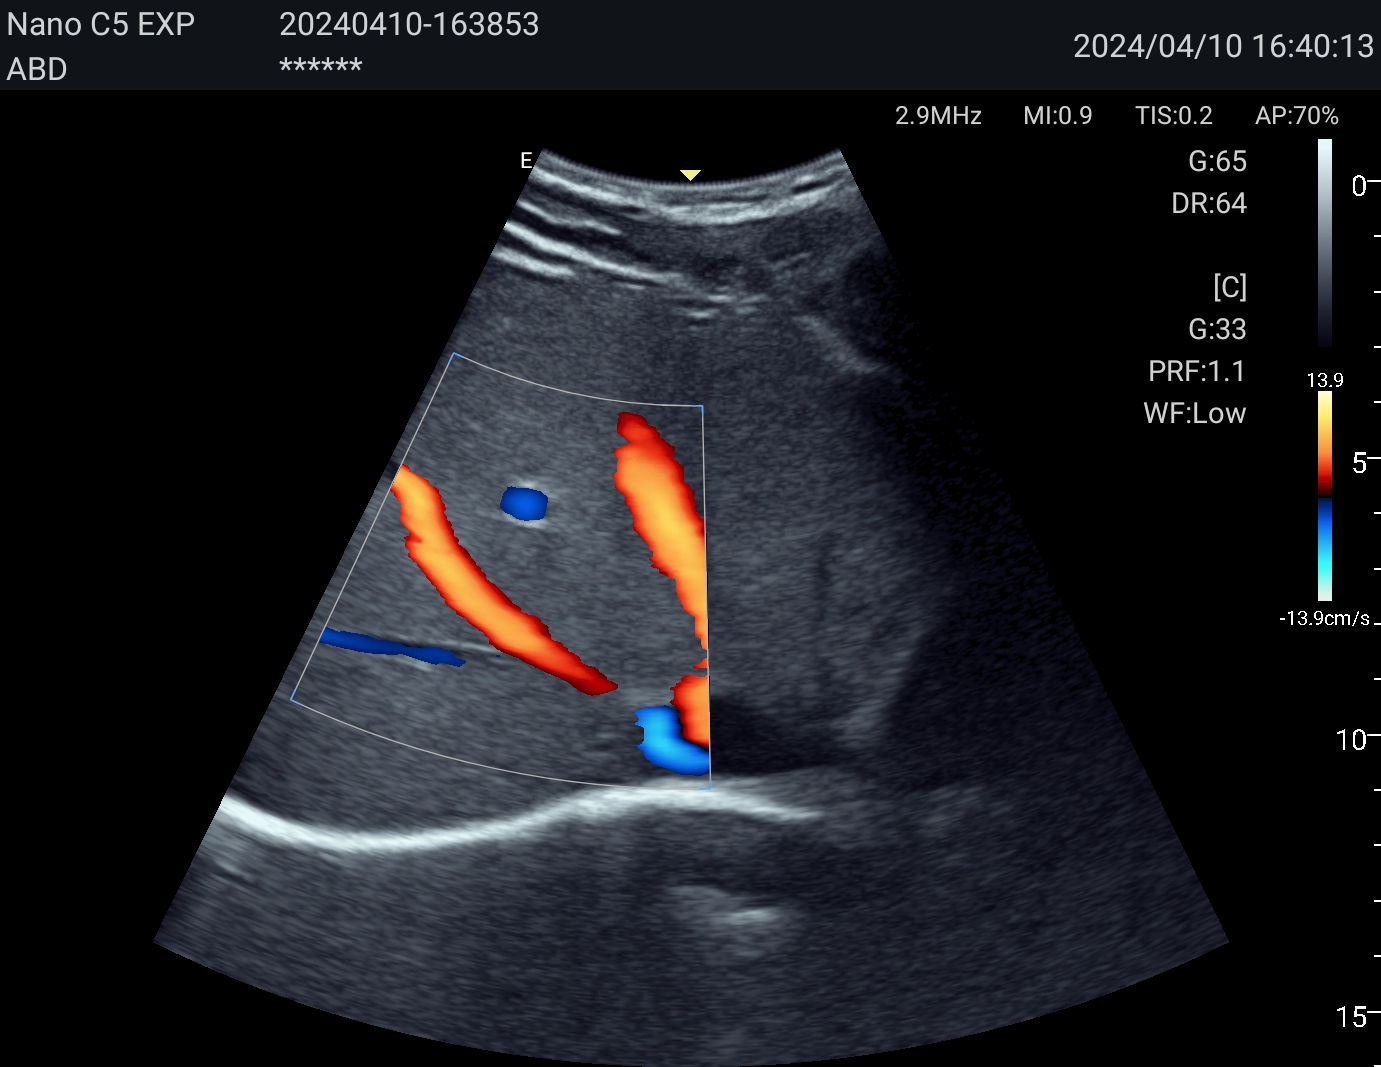

Портативная ультразвуковая система EDAN Nano, созданная на базе новейшей платформы для зональной сонографии SynSight, меняет представление о портативности и производительности в диагностике на месте оказания медицинской помощи. Это революционное устройство, обеспечивающее превосходное качество изображения в компактном корпусе, сочетает в себе передовые технологии и непревзойденную мобильность, что делает его незаменимым инструментом в динамичной клинической среде — от первичного осмотра пациентов в экстренных ситуациях и оказания помощи на месте до обследования пациентов в стационаре, ухода на дому и первичной медико-санитарной помощи.

Технология зональной сонографии — это совершенно новый подход к получению и обработке ультразвуковых изображений. EDAN SynSight может использовать всю информацию, содержащуюся в наборе эхо-данных, полученных в каждой большой зоне, и таким образом охватывать поле зрения за меньшее количество циклов передачи/приёма. Исходная необработанная эхо-информация многократно обрабатывается в процессоре канальной области для формирования оптимальных изображений.

Используйте перспективную технологию визуализации в портативном УЗ-сканере. Интерфейс устройства интуитивно понятен, а применение современных режимов сканирования обеспечивает эффективную и точную диагностику в различных клинических ситуациях. Аппарат оптимален как для работы в клинике, так и для неотложной помощи, повышая качество обследования у постели больного.